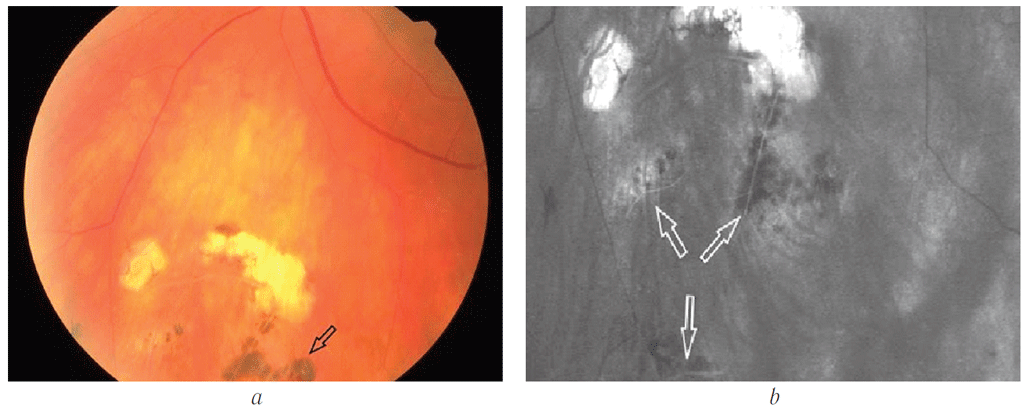

Левый глаз. Острота зрения — 1,0. Глазное дно: центральные отделы без патологии. Артерии сужены, вены расширены, их соотношение 1 : 2. На периферии сетчатки на 11 ч условного меридиана определяется самоотграниченный с пигментированными прилежащими краями дырчатый разрыв сетчатки, над ним в стекловидной камере — умеренно подвижная «крышечка» (фрагмент сетчатки, образовавшийся в результате его отрыва в процессе формирования дырчатого разрыва) (рис. 5).

Рис. 5. Сканирующая лазерная офтальмоскопия (ретрорежим), верхневнутренний квадрант периферической сетчатки левого глаза. «Крышечка» дырчатого разрыва сетчатки в стекловидном теле (стрелка)

Fig. 5. Scanning laser ophthalmoscopy (retro mode), the upper inner quadrant of the peripheral retina of the left eye. Operculum of the retinal tear in the vitreous (arrow)

С 12 до 3 ч условного меридиана на крайней периферии сетчатки визуализируются купол отслоённой сетчатки со множеством мелких складок (рис. 6, 3), а также слабопигментированная линия демаркации (рис. 6, 2). Центральнее определяется пигментный невус хориоидеи (рис. 6, 1), на 6 ч — хориоретинальная дистрофия по типу «решётчатая» (рис. 7), к которой фиксирована лента уплотнённого стекловидного тела (рис. 8).

Рис. 6. Сканирующая лазерная офтальмоскопия, ретрорежим. Верхненаружный квадрант периферической сетчатки левого глаза: 1 — пигментный невус; 2 — линия демаркации; 3 — отслойка сетчатки

Fig. 6. Scanning laser ophthalmoscopy, retro mode. Upper temporal quadrant of the peripheral retina of the left eye: 1 – pigmented nevus; 2 – demarcation line; 3 – retinal detachment

Рис. 7. Фото глазного дна (а) и сканирующая лазерная офтальмоскопия, ретрорежим (b). Нижние квадранты периферической сетчатки левого глаза: Витреохориоретинальная дистрофия по типу «решётчатая» (стрелки)

Fig. 7. Fundus photo (а) and scanning laser ophthalmoscopy, retro mode (b). Lower quadrants of the peripheral retina of the left eye. Lattice vitreochorioretinal degeneration (arrows)

Рис. 8. Оптическая когерентная томограмма периферической сетчатки левого глаза. Срез через очаг хориоретинальной дистрофии: 1 — место тракции сетчатки тяжем фиксированного и уплотнённого стекловидного тела (2)

Fig. 8. Optical coherence tomography of the peripheral retina of the left eye. Scan through the focus of chorioretinal dystrophy area: 1 – retinal traction with a fixed and compacted vitreous band (2)